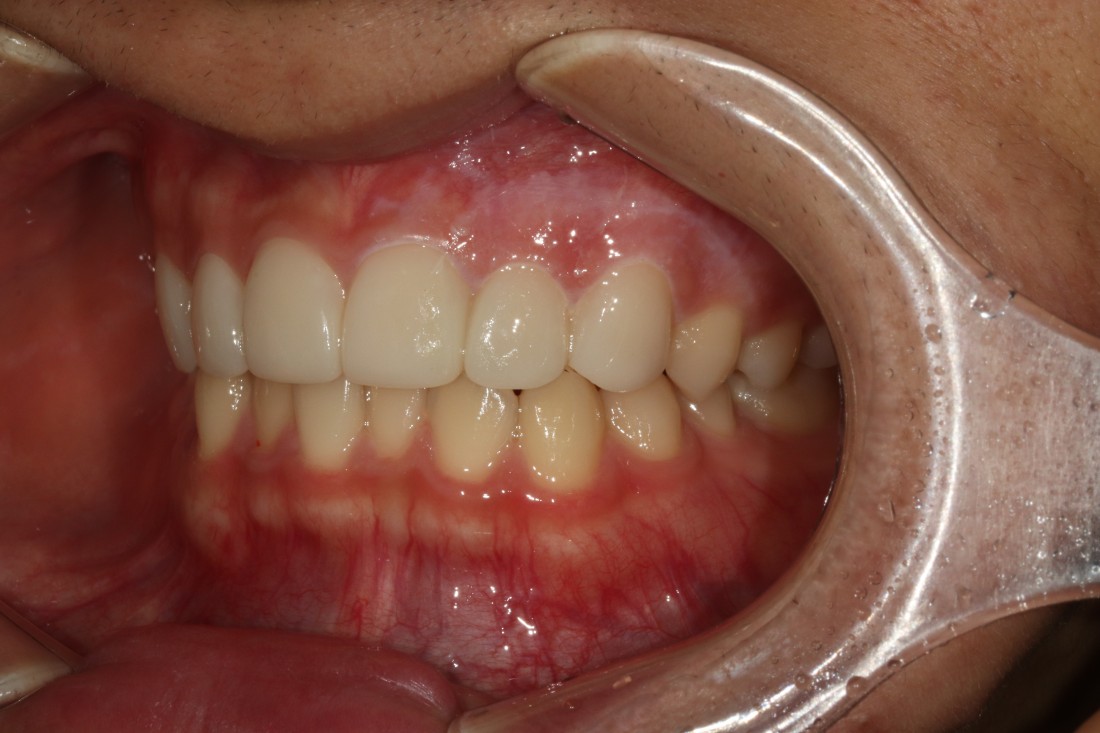

광주 라미네이트 치과는

서울 강남에서 라미네이트 진료만을

10년 넘게 담당해오고 계신

전문의 고석호 대표원장님께서

직접 상담부터 디자인, 시술 및 관리까지

모든 과정을 1:1 케어로 진료하기 때문에

서울 강남까지 가지 않으셔도

광주 라미네이트 치과에서

서울 의료진 기술과 실력 그대로

최상급 라미네이트 진료를 받으실 수 있습니다.